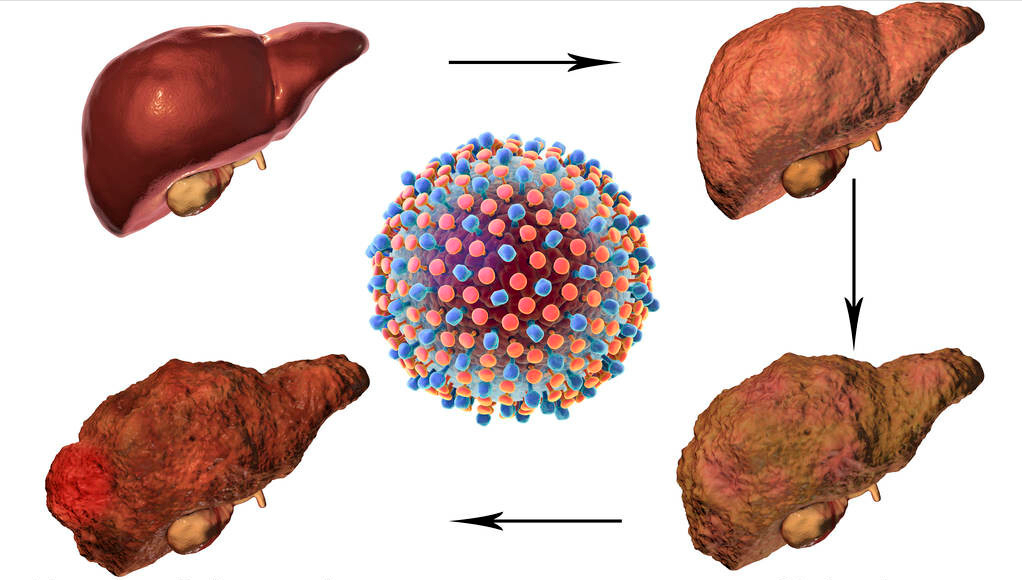

1. 得过乙肝

在我国,约有 90% 肝癌患者感染过乙肝病毒。

外国跟我们有点不一样,在西方国家,感染丙肝病毒的肝癌患者更常见。

所以,严谨地说应该是:感染过肝炎病毒的人,都要多留个心眼。

2. 有肝硬化

肝硬化的下一步往往就是肝癌,尤其是已经查出肝硬化的患者。